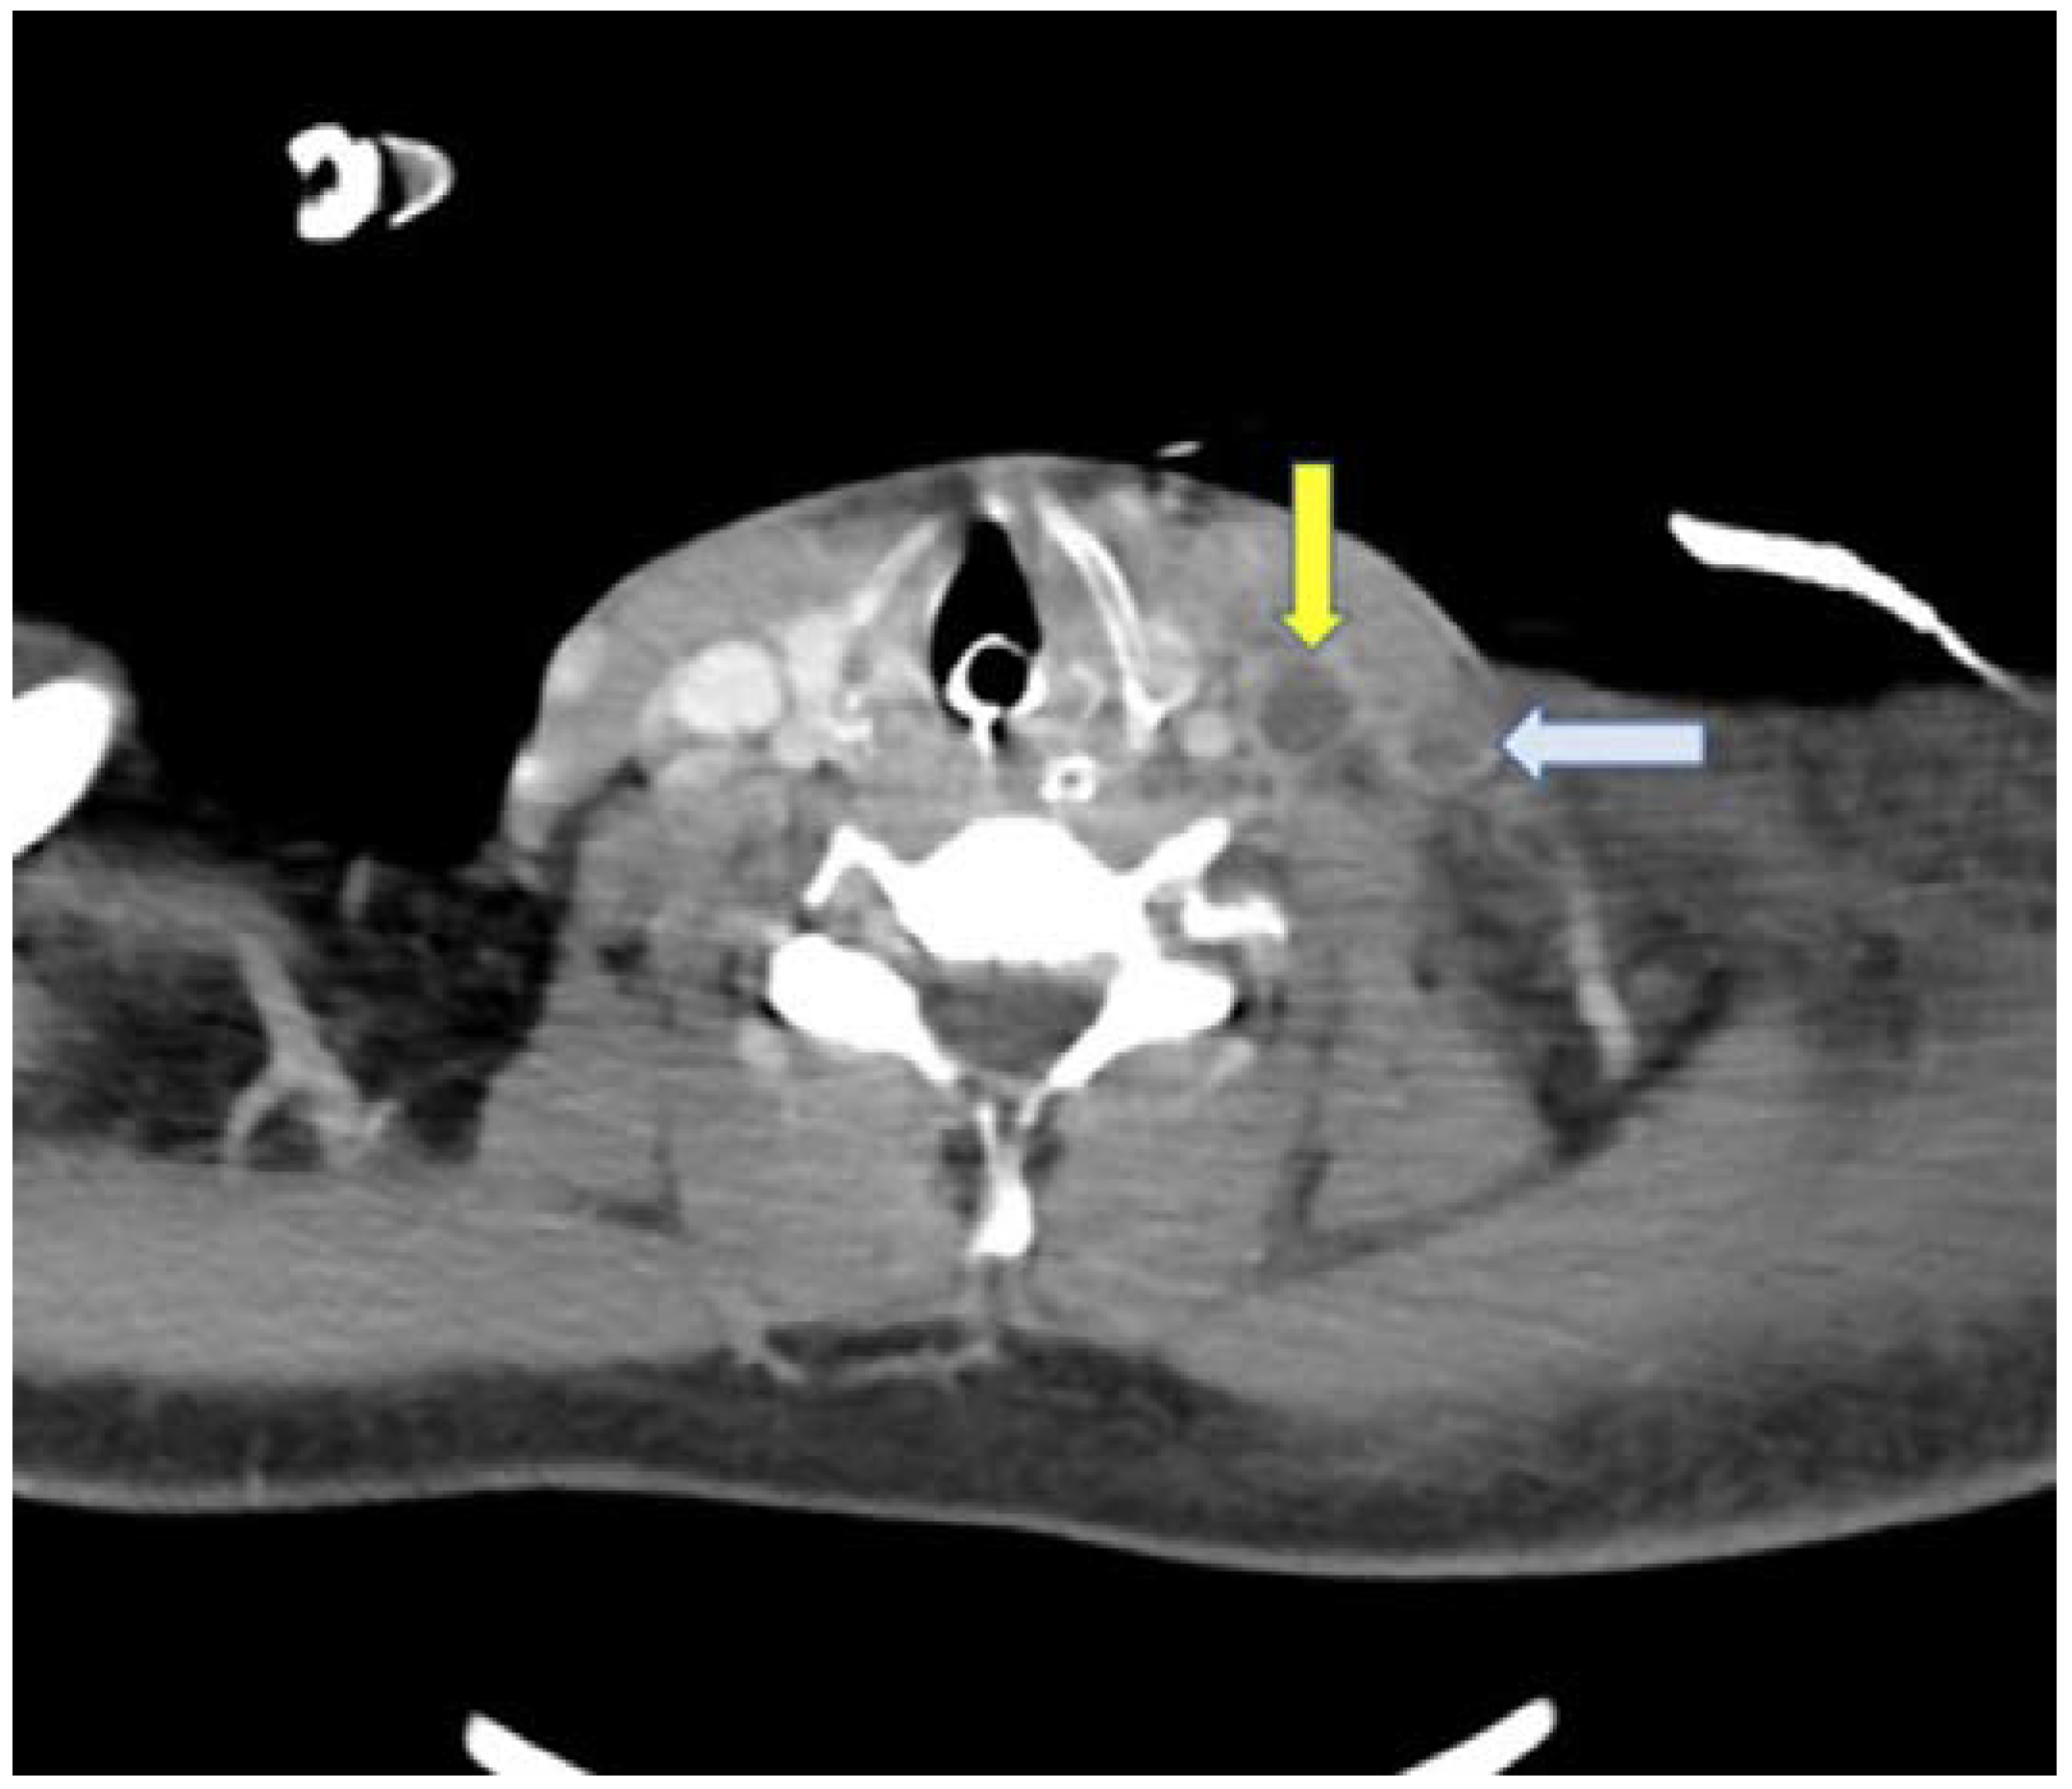

A new physical examination revealed a left cervical bulging (Figure 2) and a contrast-enhanced neck CT scan was carried out, which revealed a thrombus in the left internal and external jugular vein (Figure 3).

Figure 3. Axial view of neck angiotomography showing a filling defect in the internal jugular vein (yellow arrow) and the external jugular vein (white arrow).